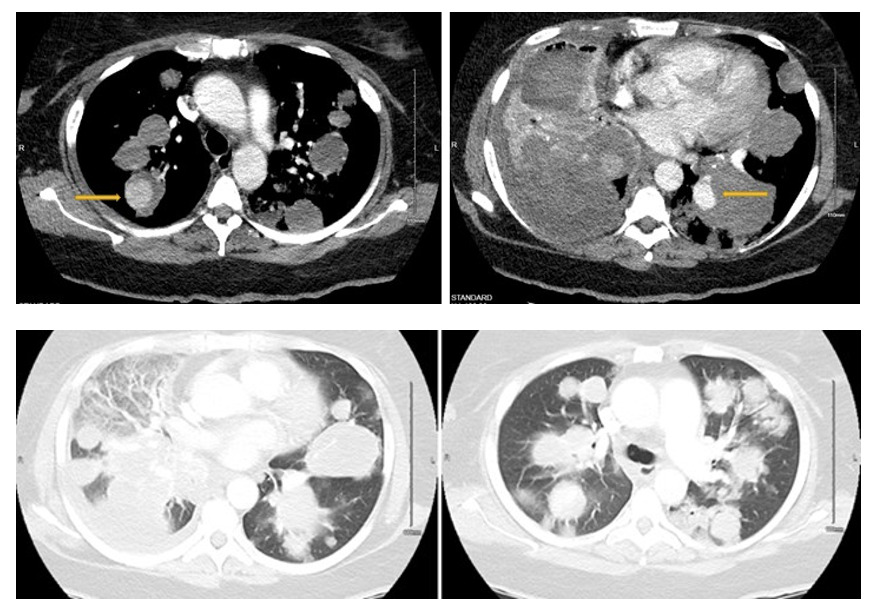

Computerized tomography angiography (CTA) showed multiple bilateral pulmonary nodules, also known as “cannonball appearance,” measuring up to 6.3 cm throughout the lungs consistent with diffuse pulmonary metastases (Figure 1). Upon admission, the patient was alert, awake, and oriented in time and space, febrile at 37.7℃, with a blood pressure of 163/95 mmHg, heart rate of 118 bpm, respiratory rate of 24 with an oxygen saturation of 97% on room air. A physical exam demonstrated a middle-aged female with increased respiratory rate and diminished breath sounds diffusely with absent breath sounds in the right middle and lower lobe on auscultation. The patient was admitted under the impression of dyspnea in the setting of diffuse bilateral pulmonary metastasis.

The patient was hypoxic throughout the hospital course which progressively worsened due to increased tumor burden. She was escalated from two two-liter nasal cannula to bilevel positive airway pressure (BIPAP) within a two-hour window. Repeat CTA twelve days after the admission was negative for pulmonary embolism but showed significant worsening of the cannonball metastases, pneumonia, a pseudoaneurysm measuring 2.5 cm in the left lower lobe within a pulmonary mass, and second pseudoaneurysm or intratumoral hemorrhage within the right upper lobe (Figure 5 and 6). In light of their worsening clinical status and widespread metastatic disease, no interventional option was suitable for the pseudoaneurysm, and since she is no longer qualified for chemotherapy, a decision to initiate palliative care was made. The lower extremity duplex was negative for deep venous thrombosis. The patient was transferred to the step-down unit under the impression of acute hypoxic respiratory failure requiring BIPAP ventilation in the setting of metastatic leiomyosarcoma with likely hospital-acquired pneumonia.